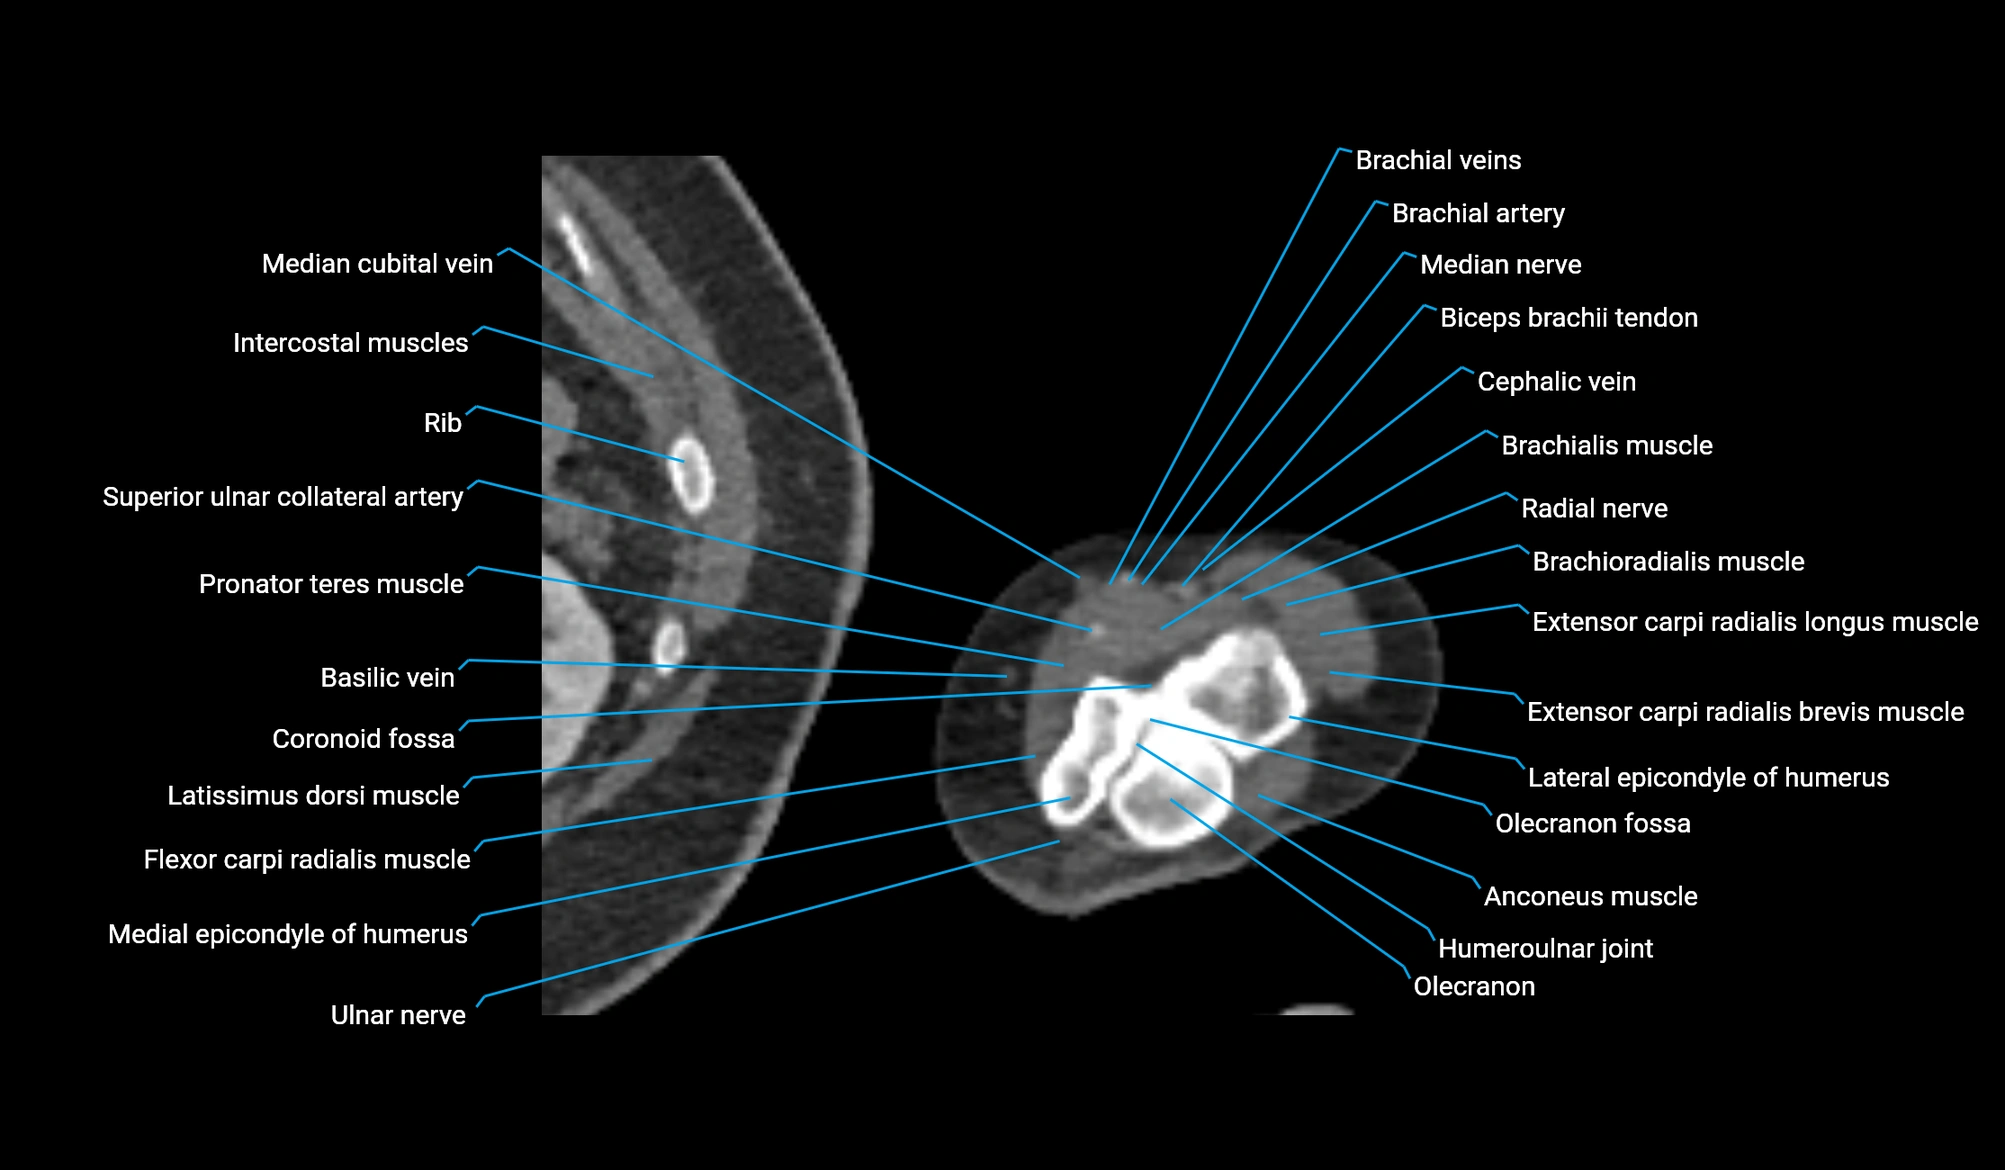

CT image